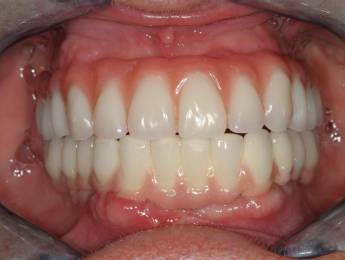

Ennek a kedves hölgynek 20 éves álmát váltottuk valóra. 20 évig hordott kivehető fogsorokat. 12 implantátum beültetése után alsó és felső fixen rögzített hidakat készítettünk. Nincs többé kivehető - evéskor, beszéd közben - elmozduló fogsor. Javult a rágási hatékonyság is, amely az egészséges táplálkozás szempontjából is nagyon fontos tényező.